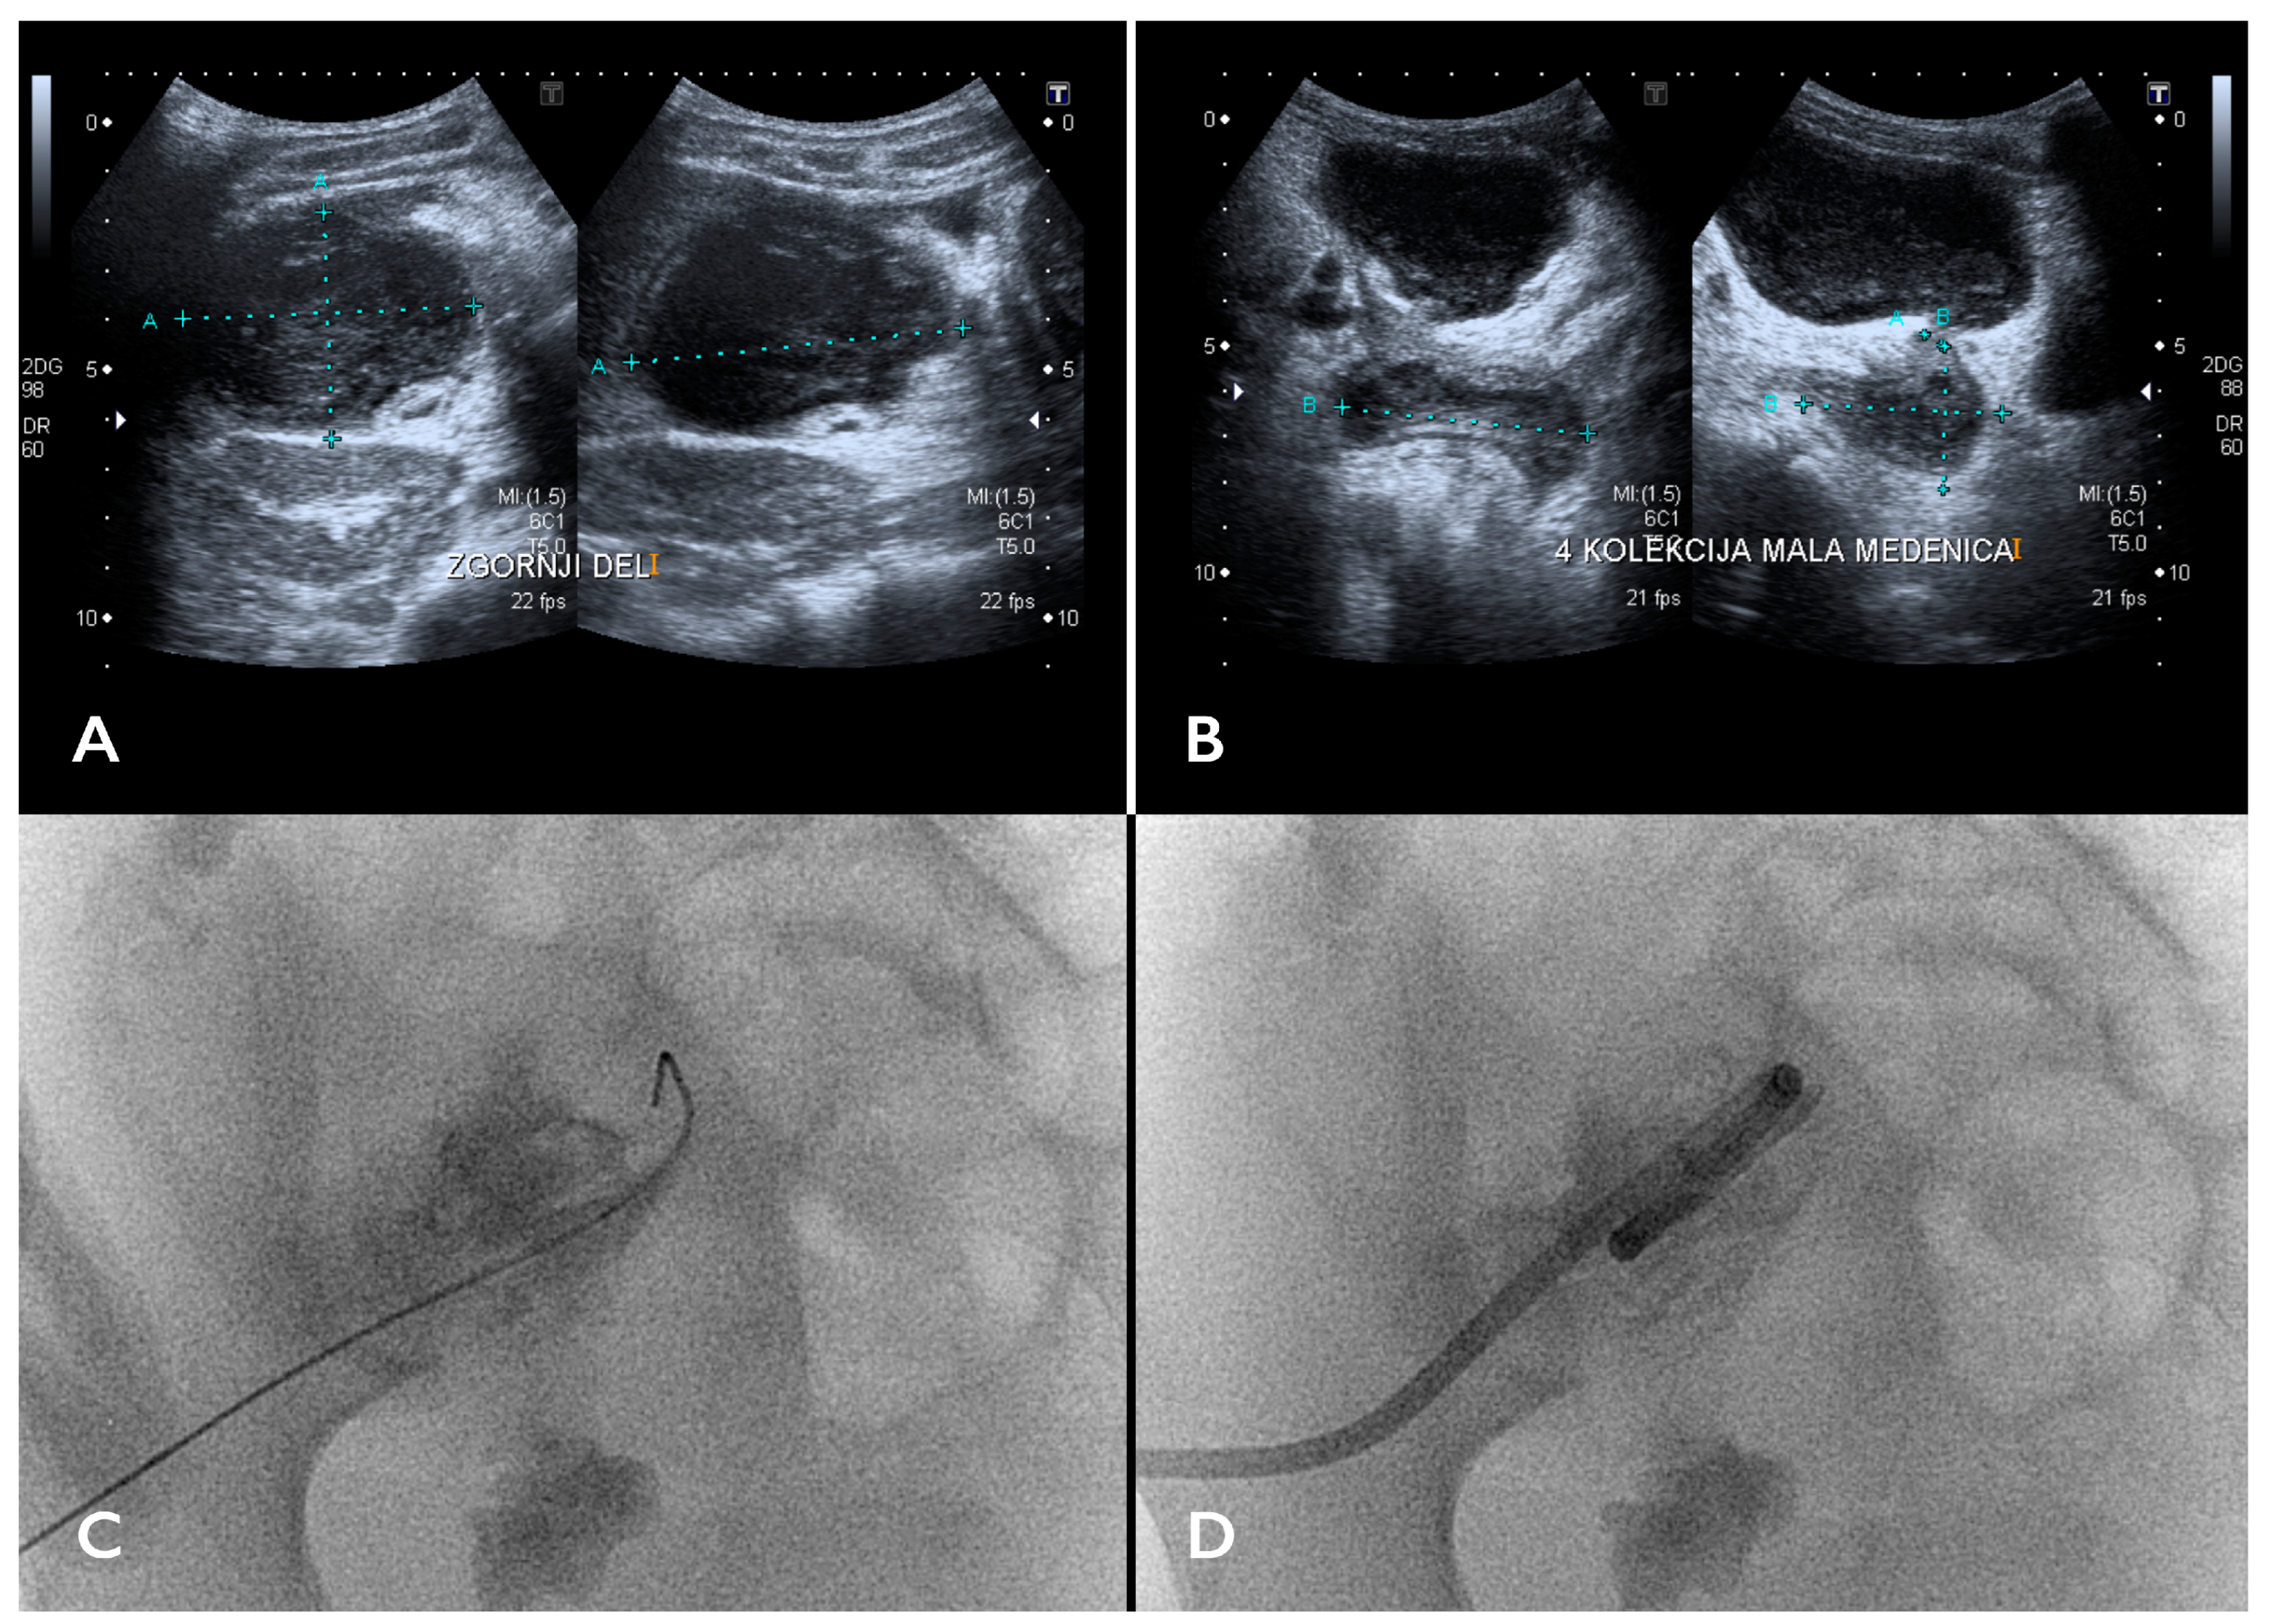

- Pereira, J.K.; Chait, P.G.; Miller, S.F. Deep Pelvic Abscesses in Children: Transrectal Drainage under Radiologic Guidance. Radiology 1996, 198, 393–396. [Google Scholar] [CrossRef]

- Chung, T.; Hoffer, F.A.; Lund, D.P. Transrectal Drainage of Deep Pelvic Abscesses in Children Using a Combined Transrectal Sonographic and Fluoroscopic Guidance. Pediatr. Radiol. 1996, 26, 874–878. [Google Scholar] [CrossRef]

| Chung T et al., 1996 [50] | Retrospective study of seven pediatric patients. | To assess the safety and efficacy of the transrectal drainage (TRD) of deep pelvic abscesses using combined transrectal sonographic and fluoroscopic guidance. | Endovaginal US was used for initial catheter guidance, followed by fluoroscopy. General anesthesia was used in all cases. Mean catheter dwelling time: 4 days. 100% clinical success. |

| Pereira JK et al., 1996 [48] | Retrospective study of 45 pediatric patients. | To evaluate the efficacy of the transrectal drainage (TRD) and/or percutaneous drainage (PD) of deep pelvic abscesses. | All the patients recovered fully—both TRD and PD are effective in treating deep pelvic abscesses. Sedation was used in 44 procedures, while general anesthesia was used in 1 procedure. Mean catheter dwell times: 4.1 days (PD) and 5.5 days (TRD). |